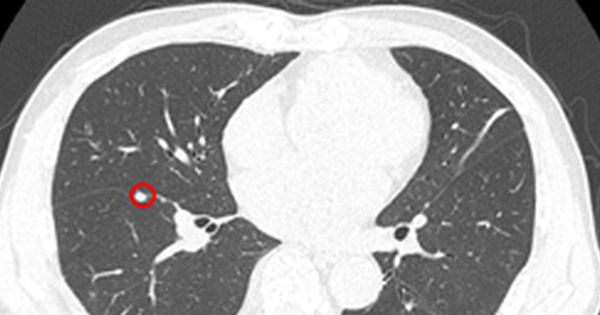

Khám phát hiện mắc cùng lúc 2 loại ung thư: ung thư phổi và ung thư đường mật, là thách thức lớn đối với bệnh nhân. Hãy cùng tìm hiểu về đa ung thư nguyên phát và những điều quan trọng xung quanh vấn...